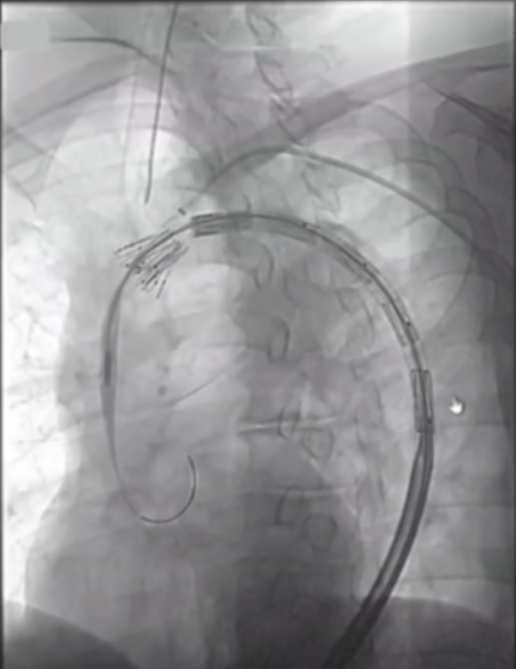

在近端密封区选择上,通常需向近端延伸25-30mm以实现更优密封效果,而定制器械凭借开窗设计,能有效增加密封长度。定制化支架技术也至关重要,支架必须精准定位,标记移动易引发开窗错位;同时要做好旋转控制,否则支架旋转不良会提升逆行夹层风险。一旦出现开窗对齐问题,可能导致I型内漏,且长期处理难度大,需借助更复杂的穿通技术纠正分支位置。

在主动脉介入治疗领域,支架设计持续创新。Terumo双分支支架采用大型矩形凹槽设计,即便旋转90度,仍能顺利接入分支,对于弓部曲线较为紧张的情况适配性更强。不过,该支架也面临技术挑战,手术中需要精准控制支架的旋转与对齐,以确保治疗效果。

深圳设计的支架同样亮点十足。它具有短输送尖端的特点,无需跨越主动脉瓣,部署过程简单,且不需要进行严格的血压控制。支架配备两个平行侧支,搭配低剖面8-9F桥接支架,在接入方式上,采用右臂入路结合左颈动脉小切口的方式,为手术操作提供了便利,也有望为患者带来更优的治疗体验。